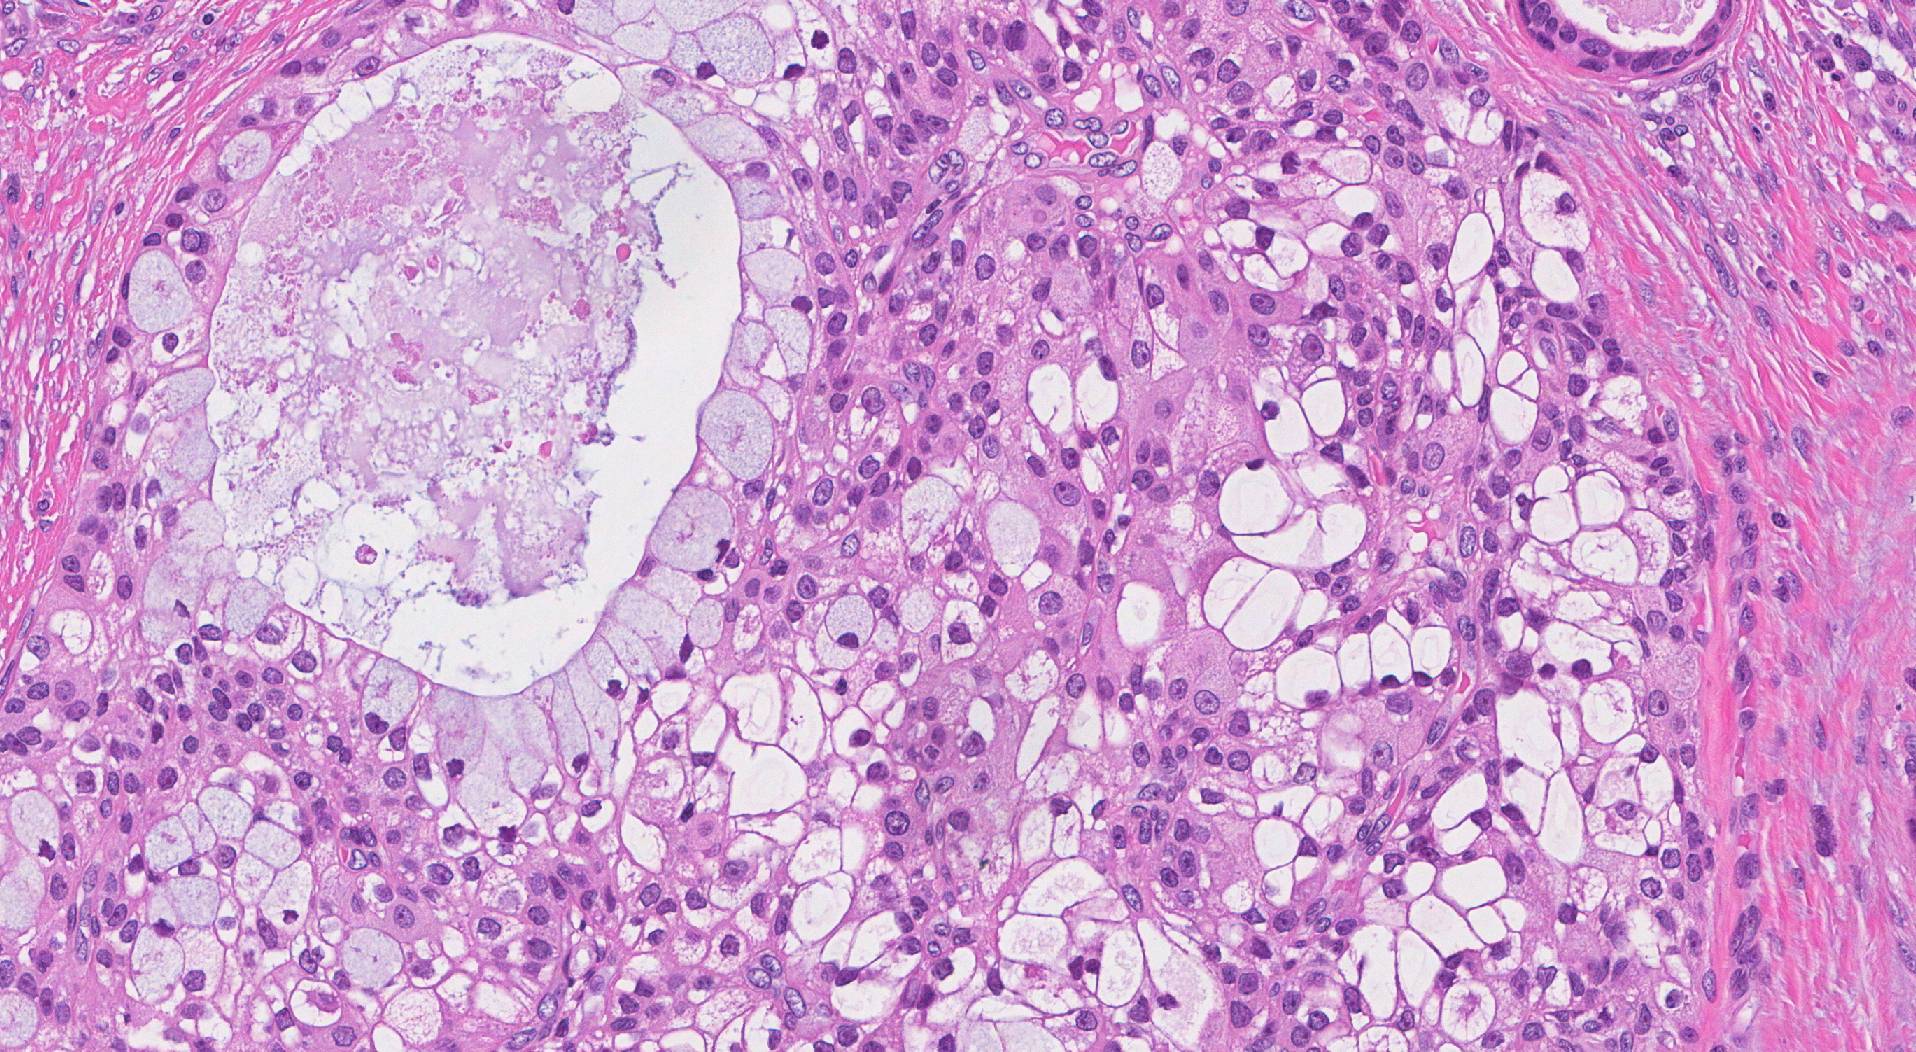

Myoepithelial Carcinoma (MC)

Myoepithelial carcinoma makes up less than 2% of all salivary gland tumours